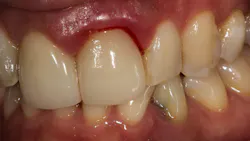

Recently several patients inquired about “why my gums still bleed” after they receive a professional cleaning with their dentists. The second question they ask is, “Is this normal?”

There are a multitude of reasons why patients may not respond properly to periodontal therapy or why their gums still bleed after a dental cleaning (figure 1).1 Of tantamount importance is to discern why previous therapy has not worked prior to reinitiating treatment or simply “giving the patient another cleaning.”